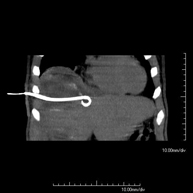

CT-guided abdominal drainage (abscesses, collections)

It consists of placing a drainage catheter over a collection of fluid located in the abdominal cavity, with the intention of emptying as much of the collection as possible. The patient should keep the drain in place for a few days, usually until it is no longer productive. It is often performed under sedation with the help of an anaesthesia team. The entire procedure is monitored using images obtained by computed tomography (CT) at various stages of the test, using CT fluoroscopy. After the test, the patient remains hospitalised. Coagulation tests must be performed before the test.